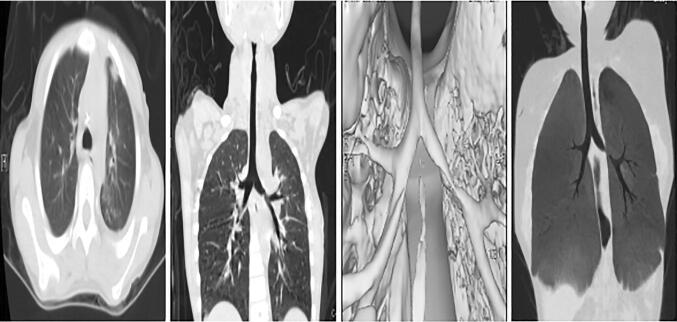

In this group, the time from trauma to diagnosis was 1–52 days (median time 27.5 days). Four cases (50%) were type I bronchial rupture, and four cases (50%) were type II bronchial rupture. One case was treated by an emergency operation. Another case was not treated with emergency bronchial rupture surgery due to another serious comorbid injury, and bronchial rupture surgery was performed 1 week after the condition stabilized. The rest performed bronchial rupture surgery at least 2 weeks after trauma. The distance between the bronchial stump and the trachea carina in all patients was approximately 2 cm. The postoperative ventilator-assisted breathing time was 8.5–129.4 h (median time: 101.4 h). There was no bronchopleural fistula after the operation. Seven patients received bronchial end-to-end valgus anastomosis, and one received right middle lobe lobectomy. There were no deaths in this group, and all patients were cured and discharged. Follow-up was conducted for 3 months to 2 years, and the patients subjected to the operation showed mild bronchostenosis within 2 weeks after trauma upon CT examination. The other six cases showed moderate bronchostenosis (Fig. 4), and they were followed-up for observation.

Fig. 4.

Postoperative CT images